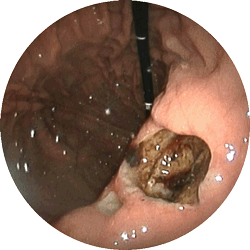

十二指腸潰瘍2

十二指腸潰瘍

嘔気(吐き気)と鈍い痛みで

来院

内服薬1ヶ月で治癒